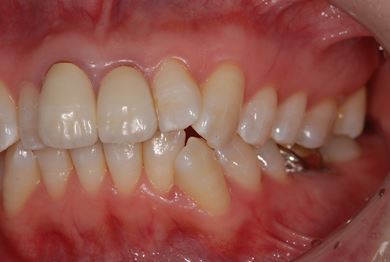

インプラント治療+セラミック治療

| 性別/年齢 | 女性 / 42歳 | ||||||||||||||||||||||||||||||||

| 主訴 | 別の病院で、右奥歯の根の部分にインプラント治療が必要と言われたので、セカンドオピニオンを希望。 | ||||||||||||||||||||||||||||||||

| 治療方針 | 右下奥、保存不能の歯を抜歯し、インプラント治療にて、機能的・審美的回復を行う。 | ||||||||||||||||||||||||||||||||

| 治療内容 | インプラント1本、メタルボンドセラミッククラウン2本(メタルボンド用土台1本) | ||||||||||||||||||||||||||||||||

| 総治療費 | 502,740円 | ||||||||||||||||||||||||||||||||

| 治療期間 | 1年3ヶ月 |